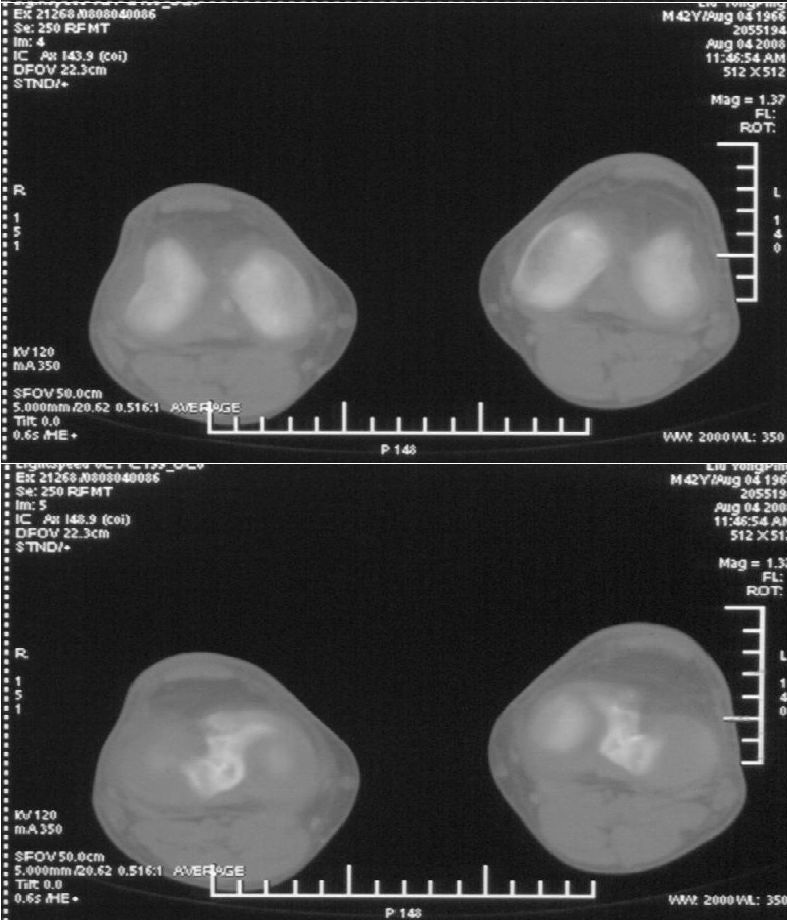

男,42岁。4个月前钢筋钝伤右侧小腿部,当时因无明显外伤,未引起重视。一周后因受伤腿部疼痛,发现肿胀,随后到当地医院进行检查(2008年4月16日)。因未发现骨质异常未引起重视,仅仅进行口服抗生素治疗处理。经过一段时间治疗但未见明显治疗效果在5月29日又进行x线检查,发现有胫骨密度上段密度增高,又进行抗炎治疗,仍未见效果。又在7月3日进行x线检查,仍然报告有胫骨上端密度增高,并建议ct检查。以下是相关检查结果:

髓腔密度呈絮状增高,胫骨上端内侧可见层状骨膜反应,考虑骨髓炎.

髓腔密度呈絮状增高,胫骨上端内侧可见层状骨膜反应,肌间隙模糊,考虑骨髓炎.

破坏、增生、骨膜反应,考虑骨髓炎

不过我想问一句,你用什么ct啊,条件竟然是kv120 ma350,我不太明白。

这个ct是ge high speeds 64排。